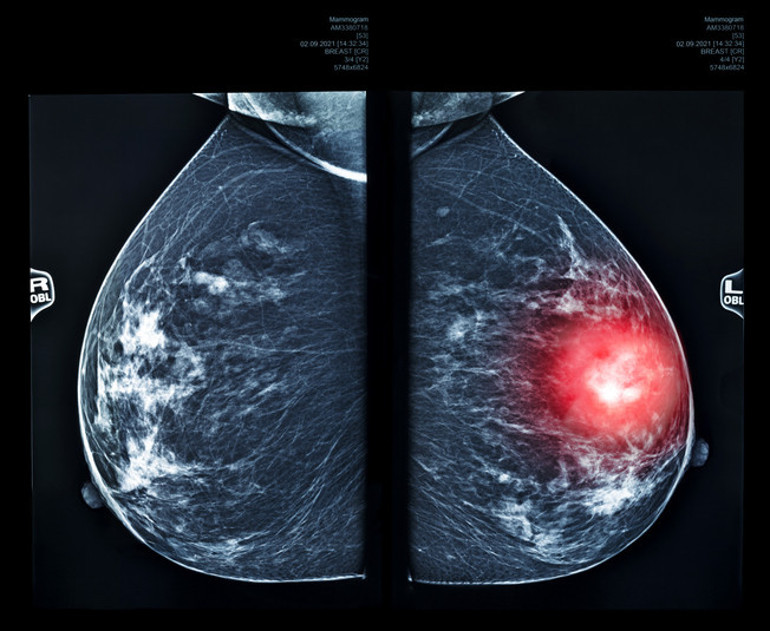

-- Meme kanserinde hafif artış (yakın dönemdeki kullanıcılar), serviks kanserinde uzun süreli kullanımda artış, karaciğer kanserinde özgül popülasyonlarda potansiyel artış belirtilmiş.

Genetik olarak meme kanserine yatkınlığı olan kadınlarda, doğum kontrol haplarının etkisinin karmaşık olduğunu söyleyebiliriz. Özellikle BRCA mutasyonu taşıyan kadınlarda meme kanseri riski zaten yüksek iken söz konusu hapların bu riski hafif artırabileceğine dair veriler de vardır. Ancak aynı haplar, bu kadınlarda yumurtalık kanserine karşı belirgin koruyuculuk da sağlayabilir. Bu nedenle ‘Grup 1’ etiketine bakılarak değil, kişisel risk–fayda dengesi değerlendirilerek verilmelidir.